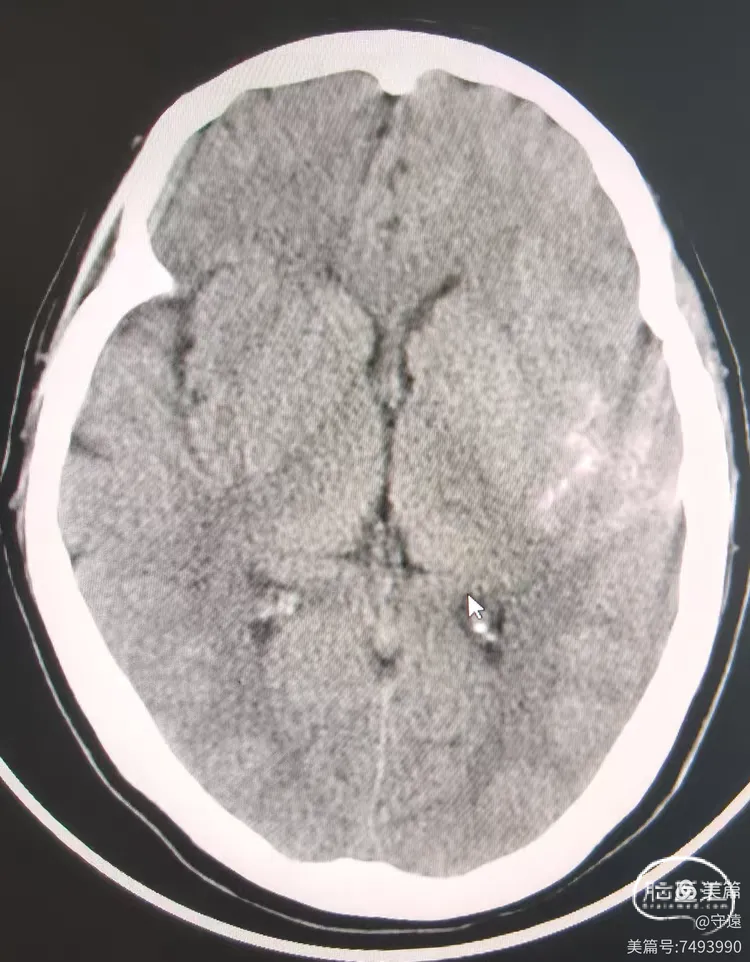

铆定狭窄位置后缓慢打压扩张至8个大气压(命名压6个大气压),泄压回撤造影,M1段血流通畅,管腔略毛糙。

推注替罗非班10mL,等待10分钟造影,血流保持3级,末置入支架。

4.ICAS病变明确,直接使用Fastunnel输送型球囊扩张导管"零交换"扩张成形,手术快捷,安全。

术后18小时复查CT左侧略高影,考虑造影剂滞留,水肿不明显。